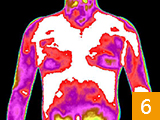

治疗前后炎症对比图/ Inflammation contrast

• 治疗前

• 治疗后